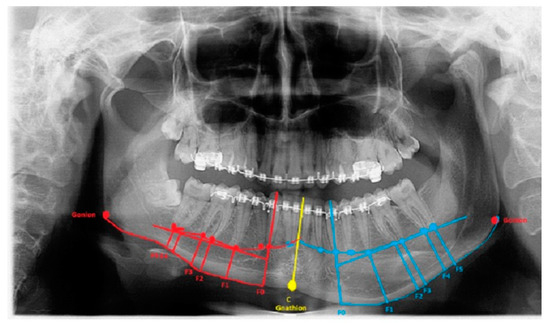

Figure 1.

Mild form of condylar hyperplasia. Red and blue lines marked F0–F5 help to visualize the distances between the tooth apex, the mandibular canal, and the mandibular base. Gonion and gnathion landmarks help to define right/left bone proportions and lengths. The yellow midline always marks the teeth and the mandibular midline. The degree of bone overgrowth and mandible angle shape and volume can be easily estimated.

Secondly, the lower border of the mandible was outlined, and a vertical line from the tip of the canine, premolars, and molars was drawn perpendicular to the outlined marginal baseline. The collected radiological (panoramic) and tomographic (CT/LDCT) data were converted and archived. The horizontal volume of the bone from the tip of the roots toward the mandibular base was measured (Figure 1). Additional landmarks were set on the course of the mandibular canal to determine the distances between the roots, the mandibular base, and the mandibular canal itself.

3.1. Mandibular Canal

The distance between the mandibular canal and the inferior mandibular border—at least 5 mm of vertical bone overgrowth (Table 2)—could indicate the usage of marginectomy. The MIB cut (approx. 5–10 mm) is performed just under the inferior border of the mandibular canal. The degree of bone excised is measured by IM and ARP (Figure 1). When the vertical bone height is limited (<5 mm) due to a low-set mandibular canal, approach three should be used. On the other hand, marginectomy or marginectomy-swing could be performed if there is ≥7 mm of vertical bone overgrowth, and the mandibular canal is positioned ≥5 mm from the MIB. While a single cut might damage the mandibular canal, altering it with two, three, or more cuts can reduce this damage due to the curved cut line. An indication for this approach is a low-set mandibular canal with irregular placement along with the MIB, according to index measurements of teeth apices F0–F5 (Figure 1; Table 1 and Table 2). The suggested measurements in preoperative radiographs on the degree of bone overgrowth influence the used surgical approaches in the authors’ proposed perspective.

The length between Go-Gn/Go-Gn and the vertical bone volume relation decreases the bone height on the opposite healthy side—the critical point of this technique is the distance between the Go-Go/Go-Gn position and the value of the F0-C bone index. In this case, approach 1C can be used with or without corrective angulotomy/anguloplasty, which reduces the angled volume on the affected side in vertical and horizontal dimensions. If both Go (Right) and Go (Left) are situated on the same horizontal line, no major surgery should be planned, unless performing a condylectomy might relocate the Go point on the affected side to a higher position afterward. Therefore, careful planning in the horizontal plane and the F5: Go measurement can help estimate whether any additional mandibular angle surgery should be planned (Figure 1 and Figure 2; Table 1). This was used in some of the authors’ cases where there was no maxillary bite-plane deviation, and no chin bone asymmetry was present.

3.3. Chin Symmetry

The chin area position in IM and ARP (Figure 1)—severe chin area asymmetry—could be treated with the surgical approach suggested by Ferguson, while smaller ones could be successfully treated conservatively by drilling and bone reshaping or with other proposed methods of marginectomy. IM is used when the distance between C and F0 is equal (1:1); when C < F0 in both the vertical and horizontal dimensions, then a leveling and/or corrective genioplasty is used by the authors (Figure 1; Table 2). After the inferior dental neurovascular bundle is wholly free and retracted, bone correction and reshaping of the new inferior alveolar nerve canal is performed. Instead of a leveling genioplasty, the remnants of the overgrowth are smoothed with surgical drills. In the authors’ system, the primary key factor is total chin correction, which is necessary in cases of severe overgrowth; when F0 > C and Go-Gn>, there is >7 mm of vertical bone overgrowth, and the mandibular canal is positioned <5 mm from the MIB. The presented measurements are novel and not used in any previous reports and should be considered an additional tool for surgery planning.

The authors indicate that a modification of the classic, horizontally performed, one-cut mandibular marginectomy—and changes consisting of two, three, or more cuts—can be used to reshape the overgrown mandibular base on its hyperplastic side. Distances measured with ARP: IM help to indicate the degree of bone resection (Table 2). It could also be used to reshape the mandibular angle on the hyperplastic side of the mandible or can be used with simultaneously performed anguloplasty and/or angulotomy—if the mandibular angle is enlarged and more square-shaped. Furthermore, this same approach can be used to avoid damage to the inferior alveolar nerve in its canal with the multiple horizontal cuts, while a single one could damage the nerve [3,4,5,6]. The tooth apices: MIB index values help in the possibility of lower border modeling estimation (Figure 1).

The authors conclude that a very severe mandibular overgrowth with increased chin involvement should be a mandatory indication for the classic Ferguson approach with a surgical reduction in the mandibular angle on the affected side [7,13]. The main reason for this is the increased distance and height of the F0:F1 and F0:C:F0 values in this study (Figure 1). The authors fully agree with Ferguson’s approach, which is confirmed in the author’s measurements based on the suggested ARP: IM values and the distances between reference points in the presented study radiographs. Two different cases of one-sided mandibular overgrowths in hemimandibular hyperplasia are drawn and explained in Figure 2.